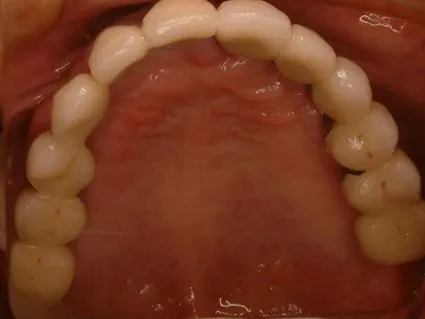

・平成20年3月8日右下34567左下34567にプラントインプラントを埋入。

・平成20年4月23日右上1234左上12345にプラトンインプラントを埋入。

・平成20年5月16日右上58左上8にプラトンインプラントを埋入。

・平成20年9月16日右上5を撤去。その後問題なく経過。